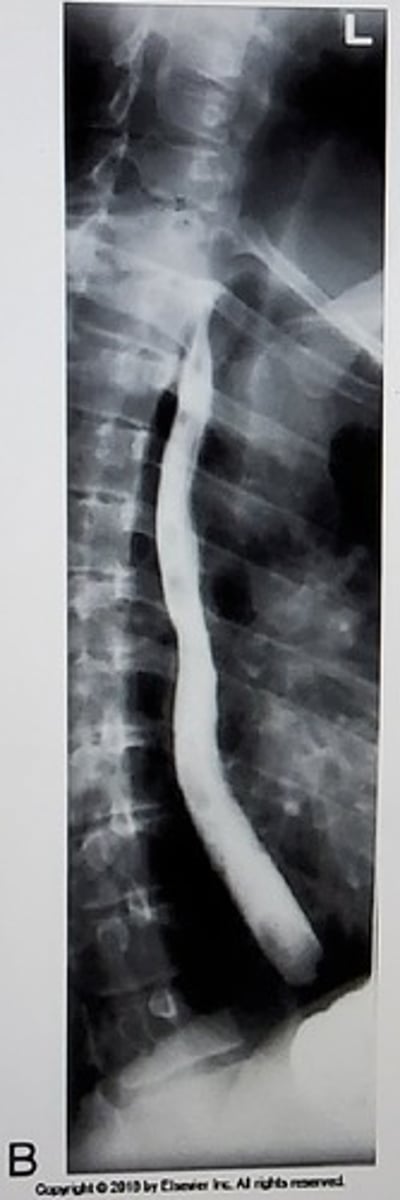

C. Left lateral decubitus

What position is this?

A. Right lateral decubitus

B. AP

D. AP axial